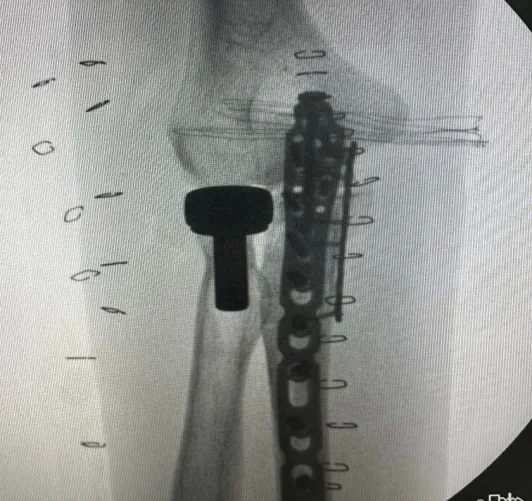

在神经从阻滞麻醉下行

尺骨骨折切开复位钢板内固定术

和人工桡骨头置换术

图片

▲ 左肘关节术后